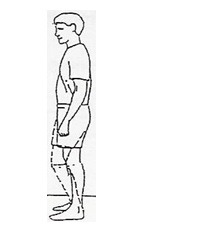

بایستید و پای عمل شده را اندکی خم کنید و همزمان با به داخل کشیدن باسن، زانو را صاف کنید. 5 ثانیه در این حالت بمانید. این حرکت را 10 بار تکرار کنید.

بایستید و پای عمل شده را اندکی خم کنید و همزمان با به داخل کشیدن باسن، زانو را صاف کنید. 5 ثانیه در این حالت بمانید. این حرکت را 10 بار تکرار کنید.

سطح ثابت و پایداری را بگیرید و خود را روی پنجهها بالا بکشید و پاشنهها را بلند کنید. این حرکت را 10 بار تکرار کنید.